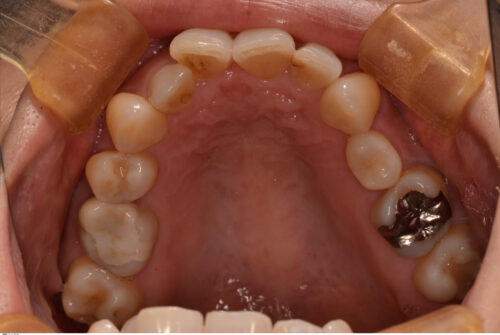

第2小臼歯は全て先天性欠損で下顎にはブリッジが入っています。

初診時のパノラマエックス線写真